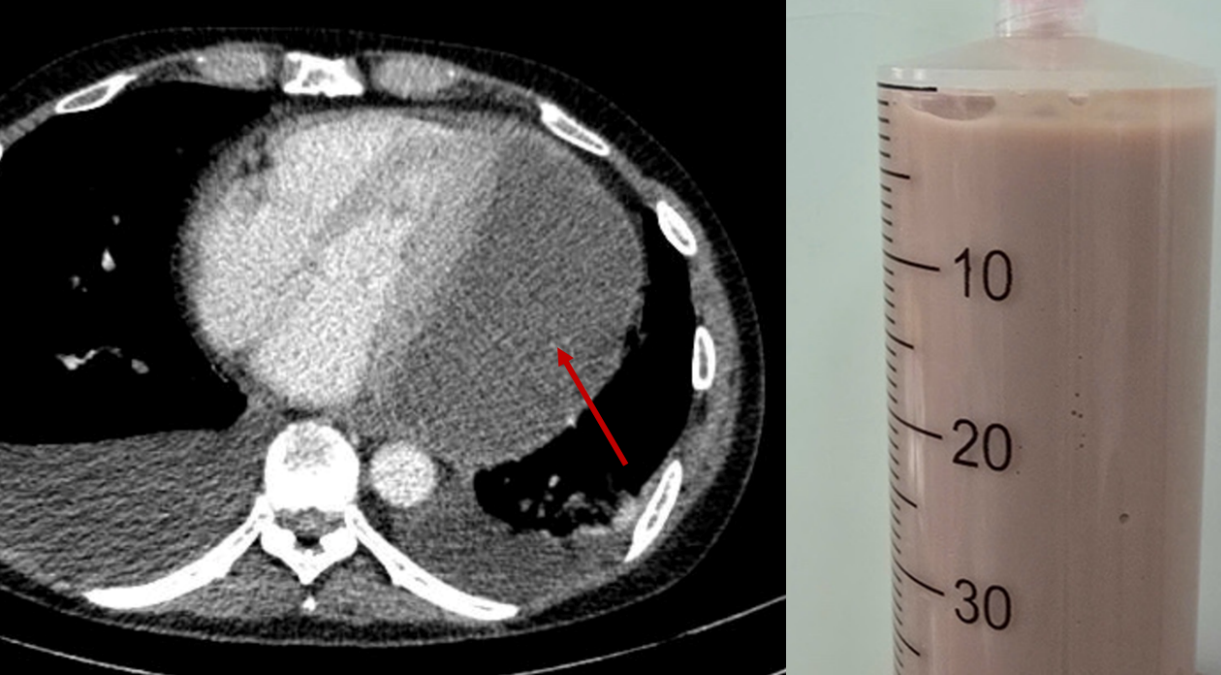

Tình trạng bệnh diễn tiến âm thầm nhưng ngày càng nghiêm trọng. Khi đến Bệnh viện Nhân dân 115, bệnh nhân trong trạng thái suy kiệt toàn thân, phải thở oxy liều cao, phù nề toàn thân, huyết áp tụt và mạch nhanh. Các bác sĩ nhanh chóng thực hiện siêu âm tim và phát hiện một khối dịch lớn gần 11cm bao quanh tim. Ổ mủ đặc quánh này gây chèn ép tim nghiêm trọng, khiến tim gần như không thể co bóp, đẩy bệnh nhân vào nguy kịch.

Nhận thấy nguy cơ tử vong cấp tính, các bác sĩ của nhiều chuyên khoa tại Bệnh viện Nhân dân 115 đã khẩn trương hội chẩn và thống nhất chỉ định chọc hút dịch mủ màng ngoài tim ngay tại giường bệnh dưới hướng dẫn siêu âm. Đây là thủ thuật khó, do dịch mủ đặc nằm sâu và sát các cấu trúc nguy hiểm của tim. Sau quá trình thao tác cẩn trọng, ê-kíp đã hút ra được 500ml mủ đặc, nhanh chóng giải phóng áp lực chèn ép, giúp tim bắt đầu co bóp trở lại.

| Các bác sĩ đã hút ra rất nhiều mủ đang bóp nghẹt trái tim giúp bệnh nhân qua nguy kịch |